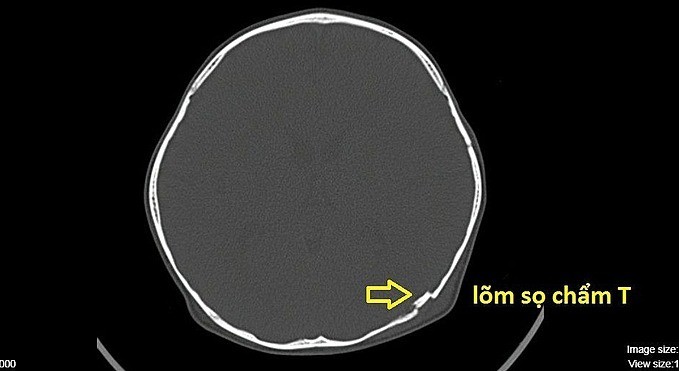

Bác sĩ Võ Doãn Tiến, Khoa Ngoại Thần Kinh, Bệnh viện quận Thủ Đức, ngày 14/1, cho biết bệnh nhi vào viện cấp cứu tuần trước. Ảnh chụp CT ghi nhận lõm sọ kín vùng chẩm trái. Mảnh xương nhỏ lõm vào não cần phẫu thuật khẩn cấp để nâng bản sọ.

Hình ảnh chụp CT cho thấy sọ của cháu bé bị lõm. Ảnh do bệnh viện cung cấp.